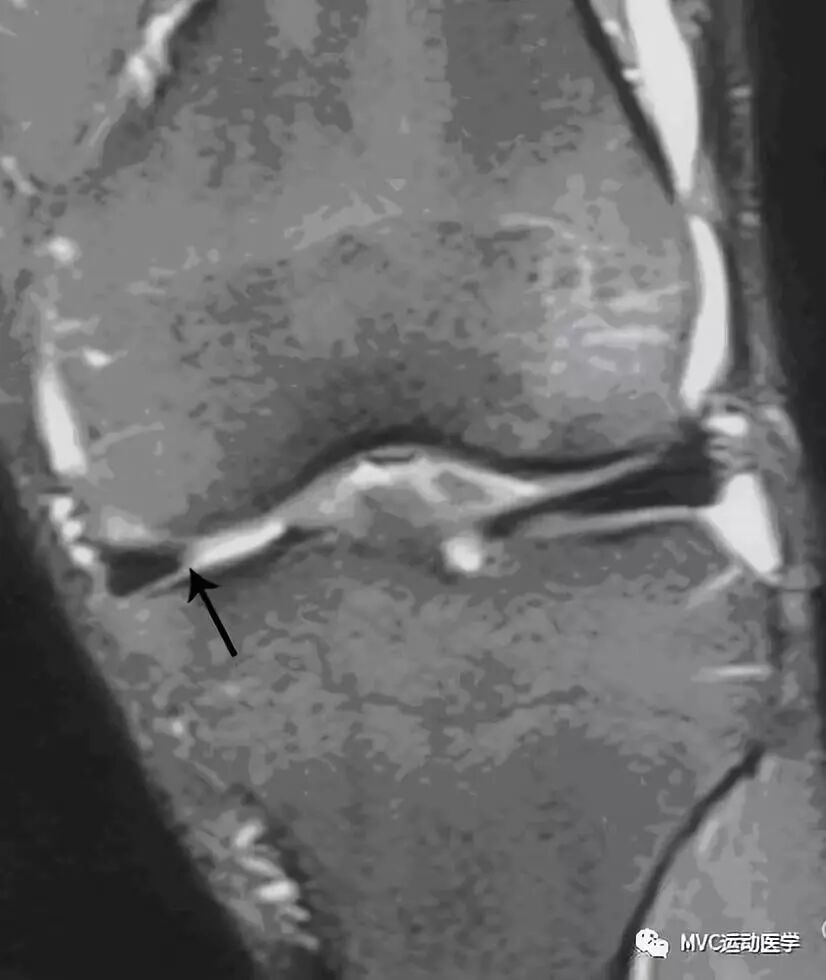

半月板游离缘磨损(黑色箭头)

纤维化的半月板形态正常。如果半月板形态异常(如离断或缩短),则考虑撕裂(放射裂或瓣状裂)。